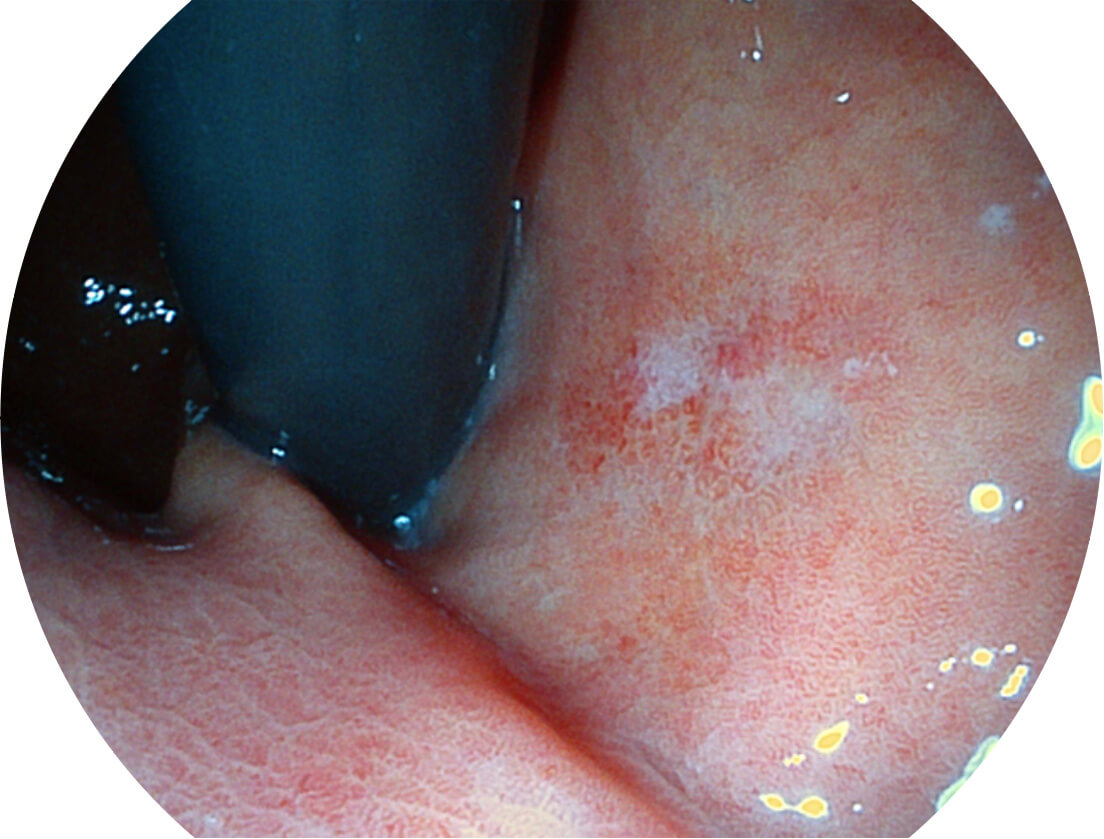

Versatile Intelligent Staining Technology, VIST

强调浅层黏膜结构的同时,保证照明亮度和提升浅层微血管与中层血管颜色对比度,病变边界更清晰。

VIST图像

采用光路合束技术,光谱自由度高,实现了更丰富的照明模式,染色模式SFI及VIST,从远景到近景,助力消化道早期疾病诊断。